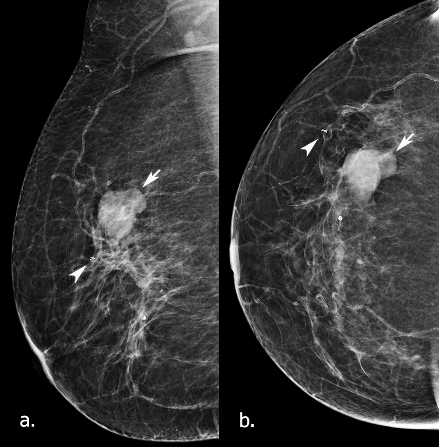

Figure 3: Mammograms in 2018. a) MLO b) CC view. At the area where the previously described cystic lesion was (arrow), in the upper outer quadrant, again, a well-defined, lobulated lesion seen, larger in size compared to 2015. Also, a marker clip is noted (arrow head), at the area of the papillary lesion that was excised under US guided vacuum procedure. It was graded as M3 (UK 5-point grading system) (equivalent to BIRAD-4a).

Three years later, in patient's new screening mammograms, at the area where the previously described cystic lesion was (at 10 o’ clock), a well-defined opacity was noted, larger in size compared to 2015 (Figure 3). Tomosynthesis views performed and an US scan followed (Figure 4), that showed a 24x12 mm, relatively well-defined cystic lesion without internal vascularity on power Doppler, with echogenic rim, thick cystic wall and internal septation. A complex cyst was reported and was subjected to a core biopsy, causing a partial collapse of the lesion. The radiological and clinical gradings were M3 U3 P2 (not palpable) in the 5-point UK classification system (equivalent to BIRADS-4) [10].